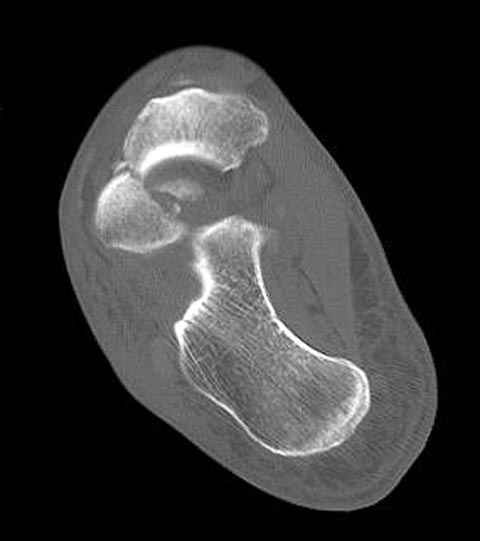

Уважаемые участники русского Ортофорума, поздравляю всех со всеми прошедшими праздниками: Новым годом, Рождеством, Hanukkah, Kwanzaa, желаю участникам всего наилучшего и здоровья.Повреждение таранной кости.Больной 81г автоавария, повреждение таранной кости, здесь снимки. Какие рекомендации?Djoldas Kuldjanov, MDDepartment of Orthopedic SurgerySt. Louis University Medical Center

Вдогонку по поводу перелома таранной кости, больная 81, не страдает диабетом, перелом закрытый, в первый же день поступления ограничились временным наружным фиксатором (как на снимке).

Планировалась открытая фиксация после спадения отека, но больная пожелала лечиться по месту жительству в другом штате..

Примеры на снимке...